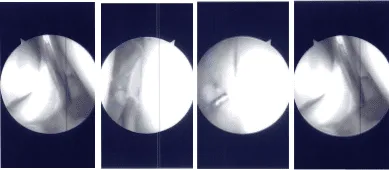

Intraoperative Arthroscopy Images

The intercondylar area was examined and the acromioclavicular ligament was found to be intact. The lateral femoral condyle was examined, and the lateral meniscus was intact. There was no cartilage damage on the lateral femoral condyle.

Now the repair of the bucket-handle tear of the posterior horn of the medial meniscus was started using FasT-Fix. Four FasT-Fix were used and taking bite, the peripheral and then the central part of the meniscus was performed.

The suture was cinched and tightened to find the good reduction of the tear. The tear was opposed well after the use of the four FasT-Fix. The chondroplasty of the patella was also done. The knee was irrigated and washed.